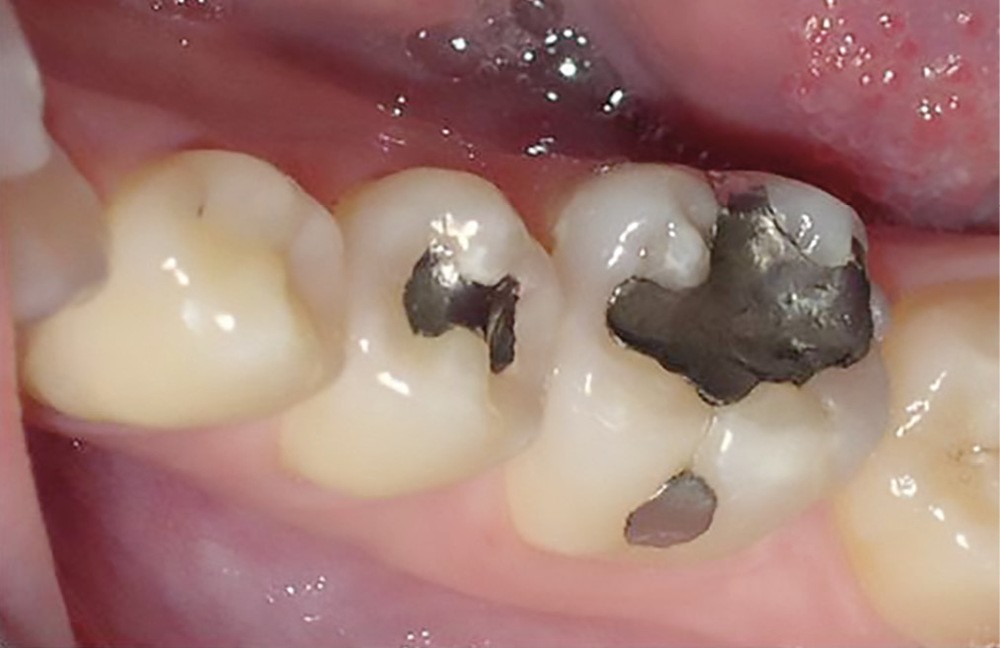

La consommation de produits acides a augmenté de manière exponentielle ces dernières années. On retrouve ceux-ci dans des aliments courants (boissons gazeuses, jus de fruit, en-cas sucré…) (fig. 1 et 2).

Nutritionnistes, médias et réseaux sociaux ont fait la part belle au régime à base de jus de citron à jeun, le matin : ce qui était présenté comme merveilleux pour le réveil intestinal et la perte de poids était en fait désastreux pour les organes dentaires, touchant de nombreuses adolescentes et jeunes femmes très sensibles à ce type de discours.

Le stress étant devenu omniprésent dans de nombreux secteurs d’activité, une frange de la population y est désormais assujettie, ce phénomène induisant ainsi de l’usure dentaire agissant en symbiose avec la prise de produits acides.

La douleur ou les sensibilités exacerbées sur des secteurs entiers ne sont plus le signal d’alarme qui fait prendre conscience au patient qu’il…